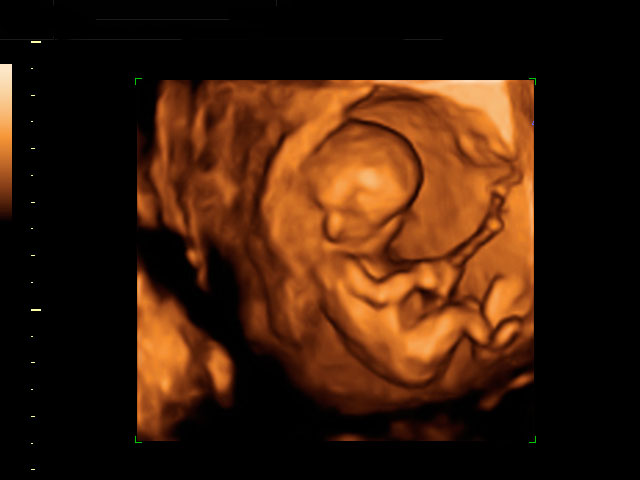

Aspecto de un bebé de 12 semanas tomado en ecografía 3D.

Se pueden apreciar con toda claridad la cabeza (aún más grande en proporción, que el resto del cuerpo), el tronco, las extremidades y el cordón umbilical. El niño ya se apoya con la espalda en el útero materno, lo que facilita la exploración por parte del ecografista.

Ecografía Embarazo 4D - SEMANA 12